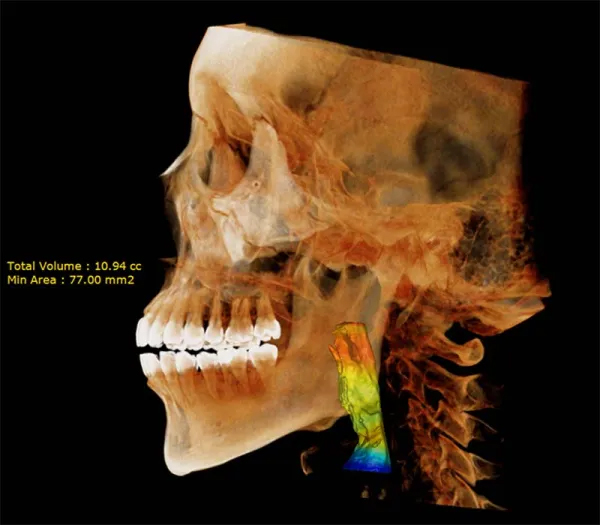

Introducing the Dentri Max, a game-changer in dental imaging tailored just for you! With its impressive Field of View (FOV) of 18 x 16.5cm, this model promises visually stunning images that redefine precision diagnostics.

Designed to cover a wide spectrum of dental needs, the Dentri Max is your all-in-one solution for endodontics, implantology, craniomaxillofacial, and cephalometric analysis. Say goodbye to blurry images and hello to crystal-clear clarity, thanks to its cutting-edge image-processing algorithm and metal artifact reduction technology.

But that’s not all – the Dentri Max goes above and beyond with features like extraoral bite-wings, FMX from panoramic shots, 3D picture superimposition, and one-step airway analysis. It’s like having a complete 2D/3D imaging package right at your fingertips, tailor-made for every aspect of your practice.

MAX 18 x 16.5 cm FOV, perfect for capturing dentition, sinus, or TMJ

18×16.5 cm FOV allows diagnosis for most maxillofacial structures

18×16.5 cm | Airway Analysis